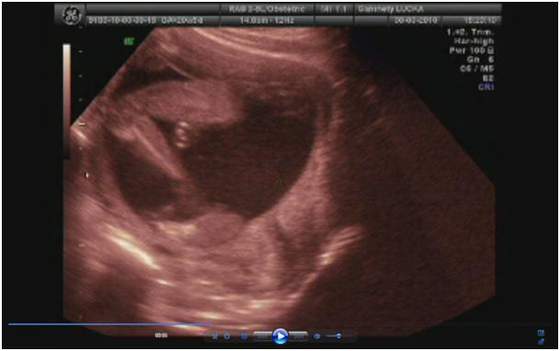

a lekarz na to "bardzo serdecznie zapraszam"

no niby 3500 ale to raczej mało możliwe (sam przyznał) skoro 2 tygodnie temu miała 2700

ale usg było jakie było i kazał się tym nie sugerować -ważne że urosła